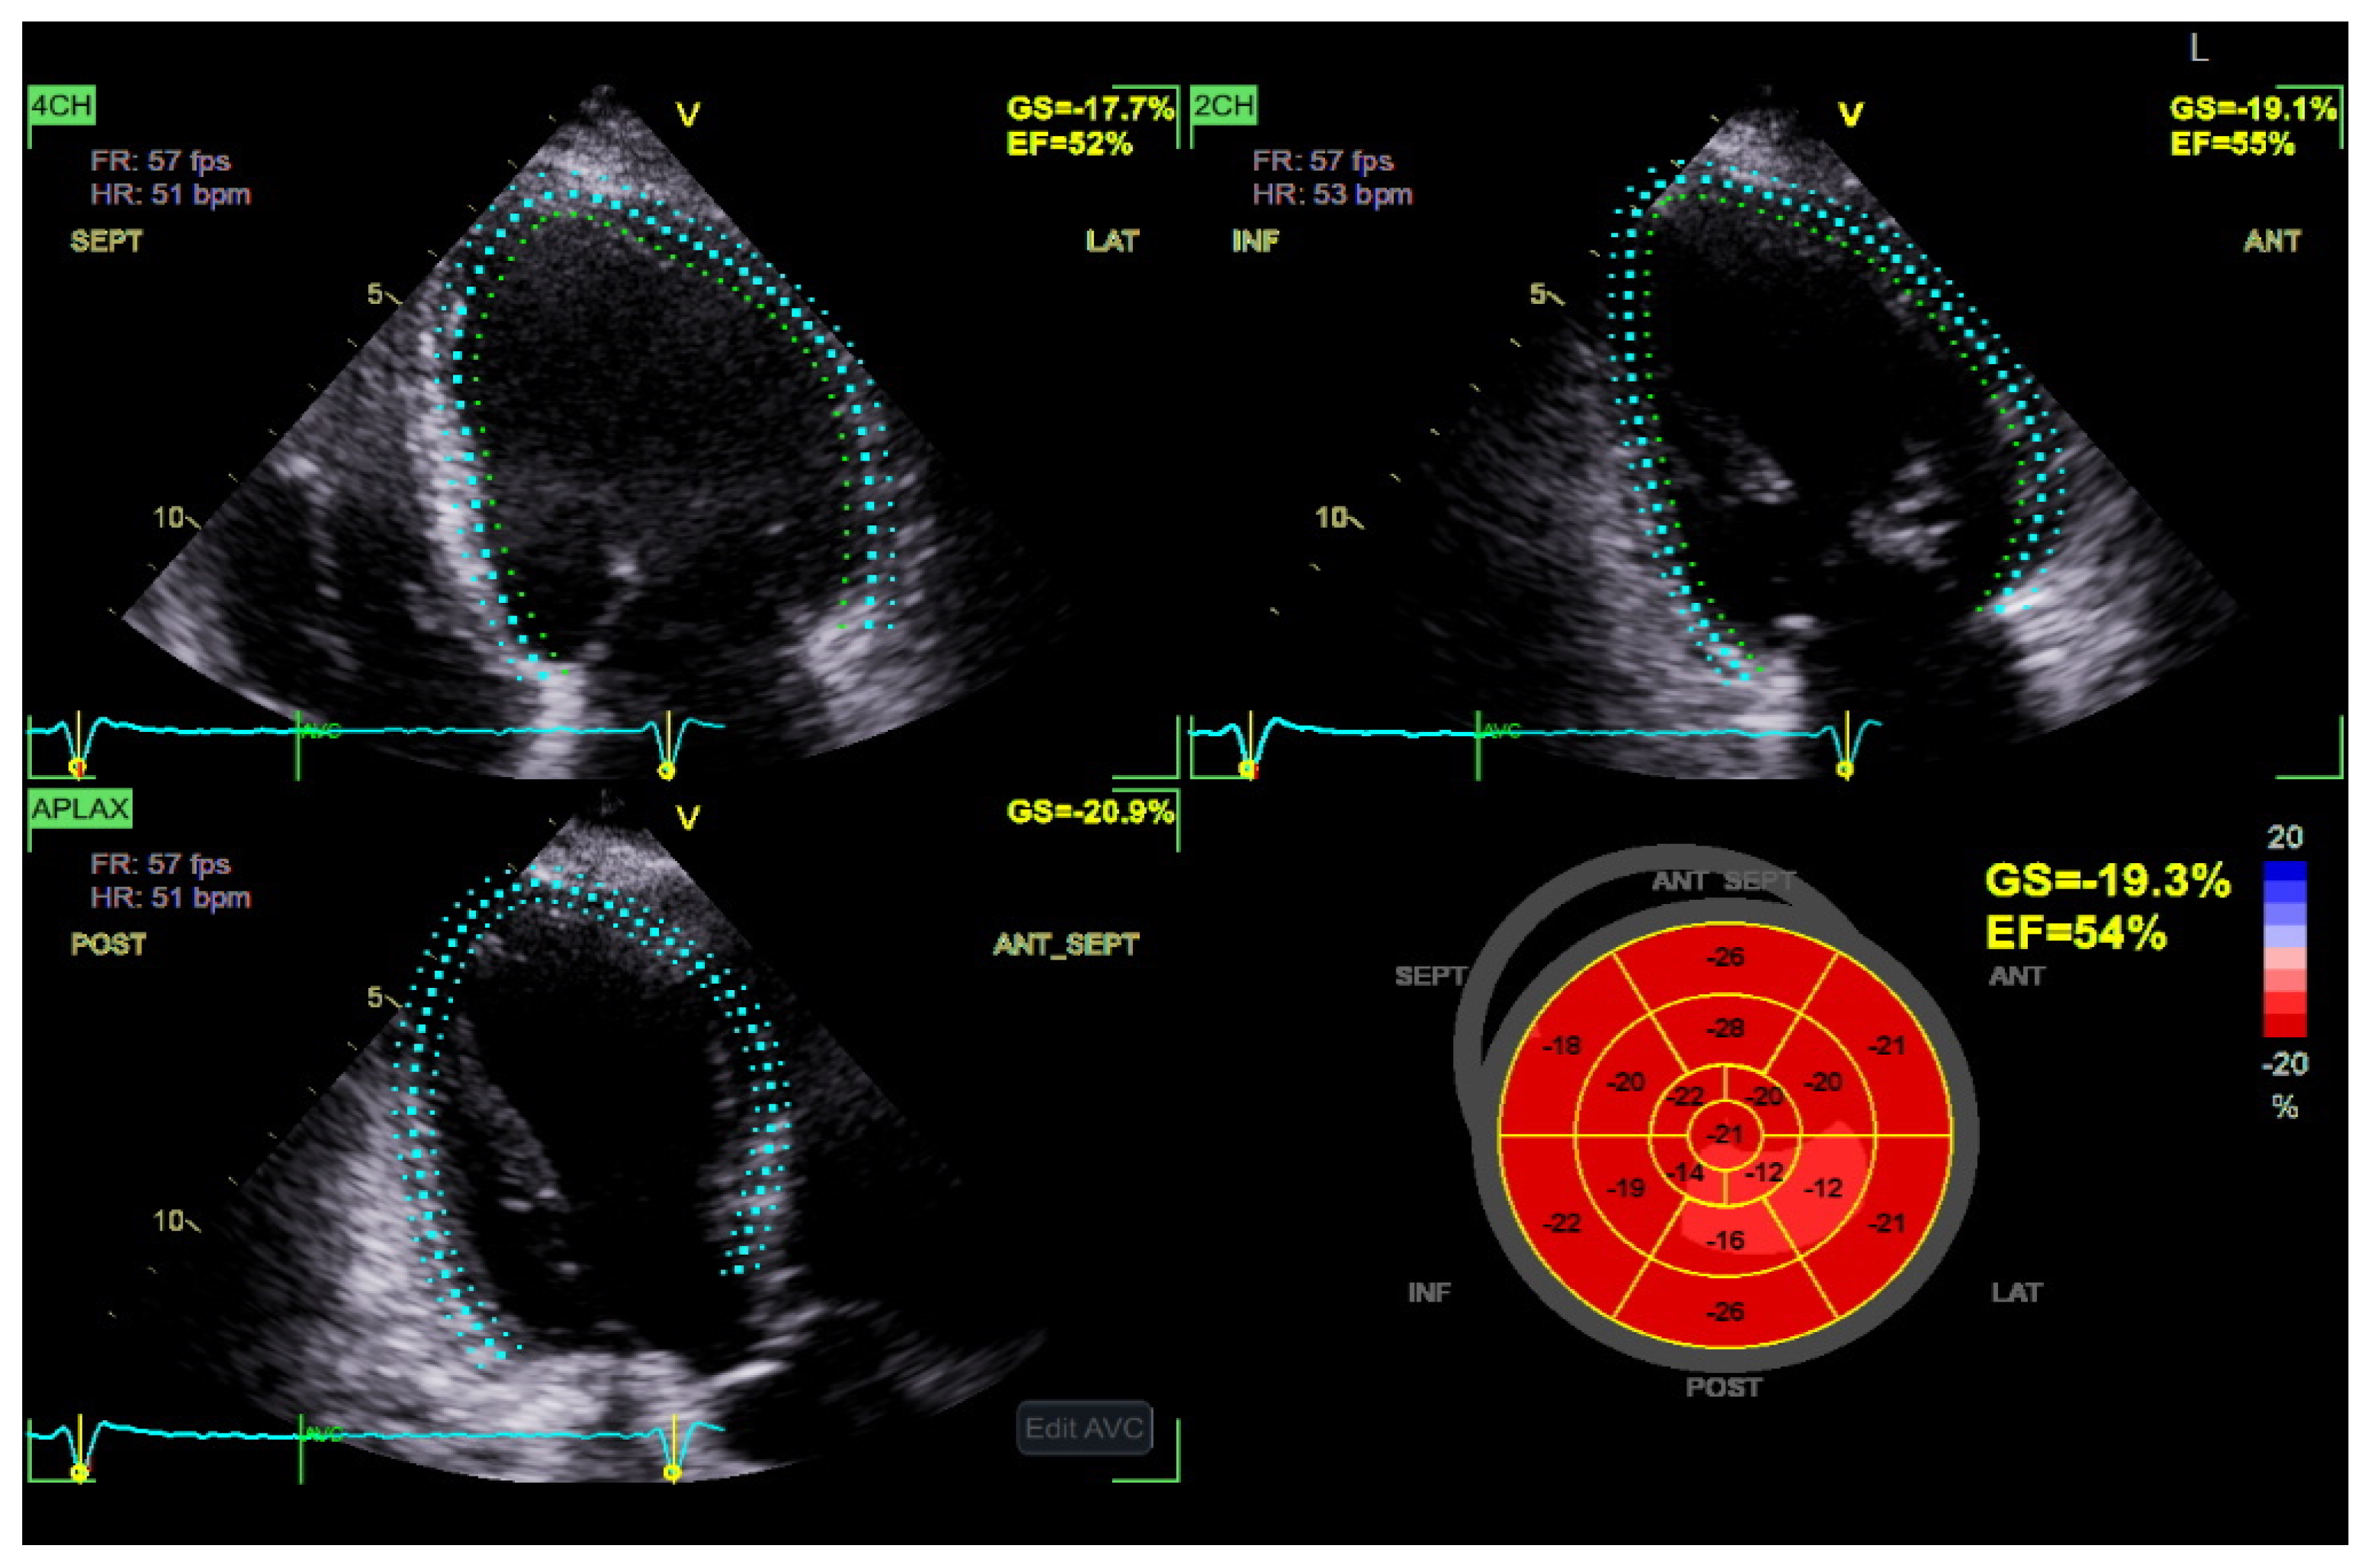

STE has emerged as a valuable imaging modality in detecting subclinical myocardial dysfunction in DBCM [68]. Traditional echocardiographic parameters, such as LVEF, often remain within normal limits in the early stages of DBCM, limiting their utility in identifying subtle myocardial abnormalities [69]. In contrast, STE enables the quantification of myocardial deformation by assessing global and segmental strain patterns, thereby offering superior sensitivity in detecting early systolic and diastolic dysfunction [69,70] (Figure 3). Among the various strain parameters, GLS has been extensively validated as a robust marker of myocardial dysfunction. Several studies have demonstrated that diabetic patients exhibit significantly reduced absolute GLS values compared to non-diabetic controls, even when LVEF is preserved [6,71]. A GLS value above −18% is considered indicative of early myocardial impairment, correlating with both metabolic dysregulation and cardiovascular risk [72]. Furthermore, longitudinal strain impairment has been shown to precede changes in circumferential or radial strain, highlighting the vulnerability of longitudinal subendocardial fibers to diabetic metabolic disturbances, fibrosis, and microvascular dysfunction [72,73].

Importantly, GLS also holds significant prognostic value in patients with DBCM. Reduced absolute values of GLS have been independently associated with adverse cardiovascular outcomes, including HF hospitalization, major adverse cardiac events (MACE), and all-cause mortality, even in diabetic individuals with preserved LVEF [74,75]. A longitudinal study by Ersbøll et al. demonstrated that impaired GLS was a stronger predictor of cardiovascular mortality than LVEF in patients with diabetes and established heart disease [76]. Moreover, in asymptomatic individuals with type 2 diabetes mellitus and normal LVEF, subclinical LV dysfunction identified by impaired GLS was shown to be an independent predictor of all-cause mortality and hospitalization over nearly a decade of follow-up [77]. Complementing these findings, reduced absolute GLS has also been linked to myocardial microvascular dysfunction even in the absence of overt fibrosis, suggesting that impaired strain reflects early, preclinical myocardial injury in diabetic populations [78]. The above notions support the incorporation of GLS into routine echocardiographic evaluation for risk stratification in DBCM, facilitating earlier identification of high-risk patients who may benefit from closer surveillance or early therapeutic intervention. As such, GLS offers not only diagnostic but also prognostic utility, reinforcing its central role in the evolving echocardiographic assessment of diabetic myocardial involvement.

Beyond GLS, global circumferential strain (GCS) and global radial strain (GRS) provide complementary insights into myocardial deformation. While GLS typically declines first, GCS and GRS impairments become more evident as the disease progresses [75]. Additionally, segmental strain analysis using STE has revealed that the basal and mid-segments of the left ventricle are more affected in DBCM, which may play a role in diastolic dysfunction and increased myocardial stiffness [79].

Although strain imaging provides greater sensitivity than conventional imaging modalities its accuracy depends on image quality and remains affected by inter-vendor variability. While reference ranges for global longitudinal strain have been proposed, universally accepted cut-off values are still lacking which limits their broad clinical adoption.